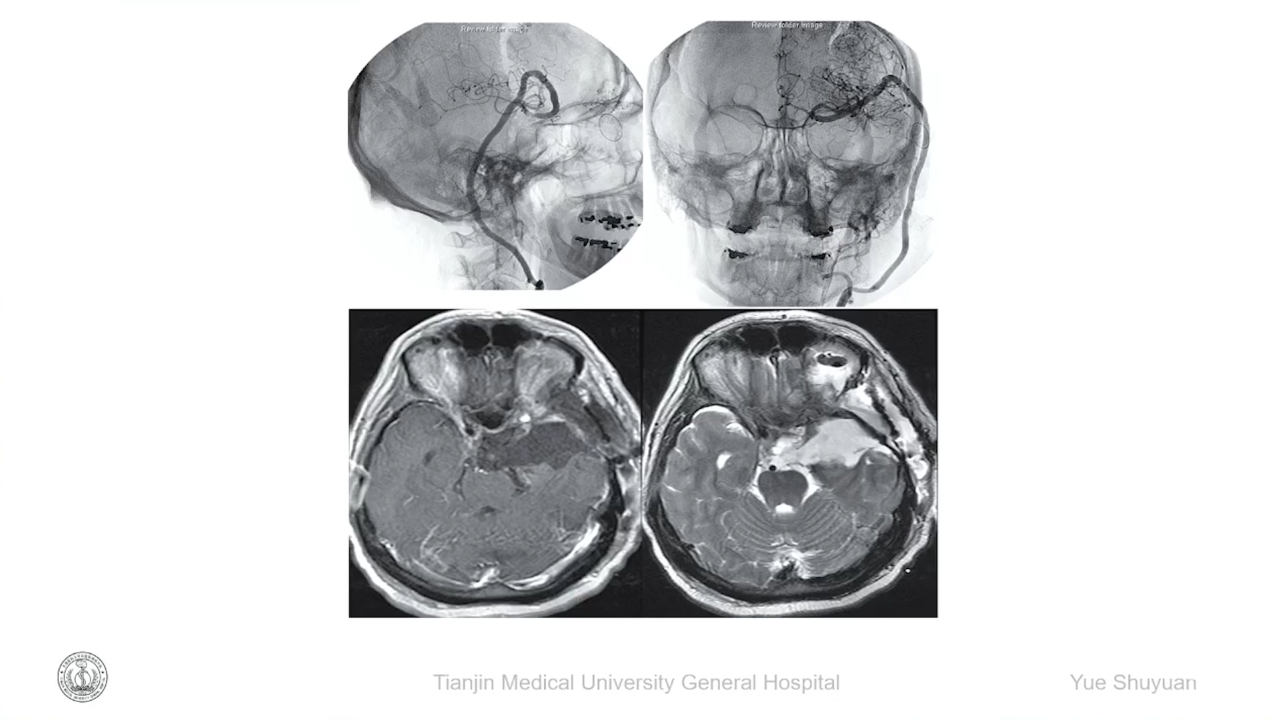

岳树源教授:高流量大桥辅助切除累及颈动脉的海绵窦区肿瘤

会议内容截图